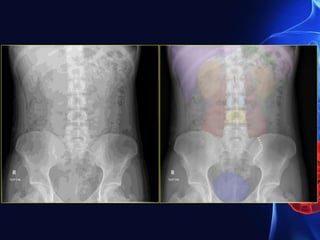

Signs of acute appendicitis in plain film

• Appendix calculus (0.5-6 cm)

• Sentinel loop-dilated atonic ileum containing a fluid level

• Dilated caecum

• Widening of the properitoneal fat line

• Blurring of the properitoneal fat line

• Right lower quadrant haze due to fluid and oedema

• Scoliosis concave to the right

• Right lower quadrant mass indenting the caecum

• Blurring of the right psoas outline-unreliable

• Gas in the appendix-rare, unreliable